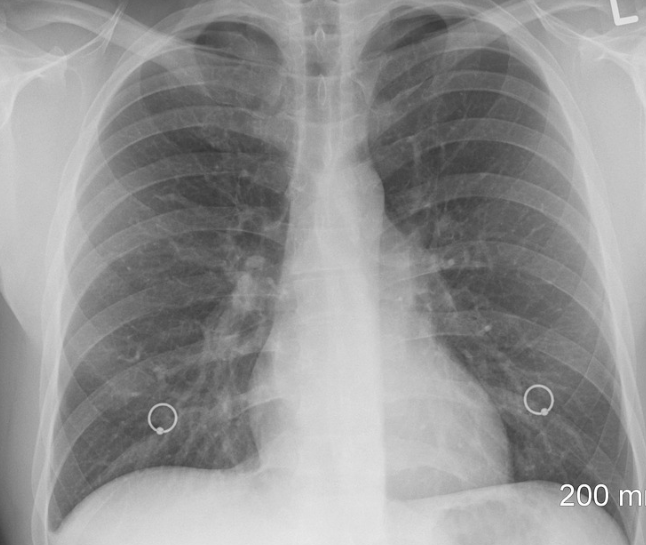

지금 중국에서 유행하는 걸어다니는 폐렴 마이코플라즈마 폐렴이 유행 중에 있습니다.

이 폐렴은 박테리아와 비슷한 마이코플라즈마 폐렴균에 의해 감염이 되고 현재 의학으로는 항생제로 치료가 가능한 병입니다.

마이코플라즈마 폐렴 증상

주요증상으로는 가슴이 답답하고 기침과 두통, 미열이 나타납니다.